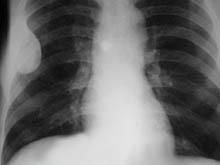

1.X線檢查病變發生於骨幹或近乾骺端一側皮質骨內,不累及骨骺,病灶呈偏心性膨脹性改變,多為不規則的單囊或多囊形,輪廓清晰,邊緣硬化,病變一般不穿破骨皮質,無骨膜反應。病變範圍廣泛者,可致患骨明顯畸形。